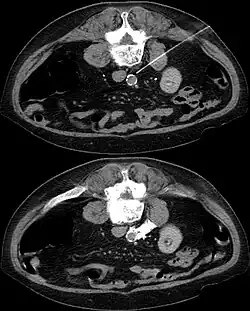

- Ausschaltung der Ganglien durch Injektion von Alkohol oder Phenol gemischt mit einem örtlichen Betäubungsmittel. Die Lage der Nadel wird durch computertomographische Aufnahmen überwacht. Unerwünschte Wirkungen sind ähnlich wie bei den operativen Eingriffen, allerdings seltener. Komplikationen werden mit ca. 2 % angegeben, Symptombesserung mit 38–32 %.